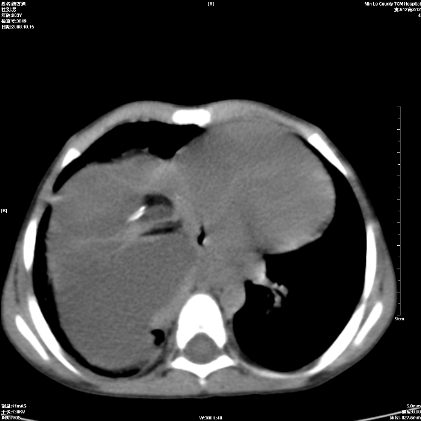

标题: PED1609:男性,3岁。彩超示肝Ca. [打印本页]

标题: PED1609:男性,3岁。彩超示肝Ca.

考虑后纵隔恶性畸胎瘤伴肝内多发转移可能性大,右侧肾上腺转移不除外.

3岁;肝低密度灶;有钙化;有转移灶;考虑肝母细胞瘤;查afp

考虑神经母细胞瘤并肝转移

考虑:1、右侧后下纵隔畸胎瘤。

2、肝脏多发血管内皮细胞瘤。

建议:增强确诊。